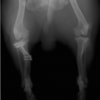

左後肢の挙上を主訴に来院されました。触診にて両関節の前方引き出し兆候、両膝蓋骨の内方脱臼を認めました。関節液検査より免疫介在性多発性関節炎は否定的でした。レントゲン検査にてfat pad signを伴う関節炎が認められたことから、前十字靭帯断裂と膝蓋骨内方脱臼(左GradeⅢ 右GradeⅢ〜IV)併発と診断し、手術を行いました。

手術は片足ずつ行い、両膝とも術中の関節鏡検査にて前十字靭帯の完全断裂と半月板損傷を確認しました。TPLO、半月板切除と滑車溝形成を始めとした膝蓋骨脱臼整復術を実施いたしました。膝蓋骨の安定化を測るために外側支帯を強固に縫合し、内側支帯は切除し縫合せずに開放状態にしています。

術後の歩行状態は良好です。

術前正面像

術前のTPAは左後肢33.1°右後肢26.8°でしたがTPLO実施により左後肢5.5°右後肢12°に矯正されました。